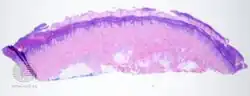

- Talon noir-pathology